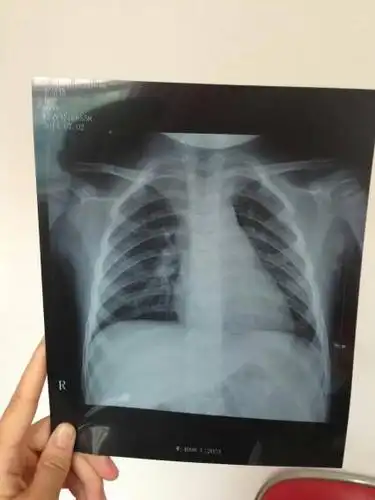

女童未及时就医诊断小儿支气管肺炎联合用药得以缓解

小孩四岁发烧不退诊断为肺炎,帮忙看下两次片子是否好了

宝宝一岁支气管肺炎

儿童胸片 大家帮忙分析一下!